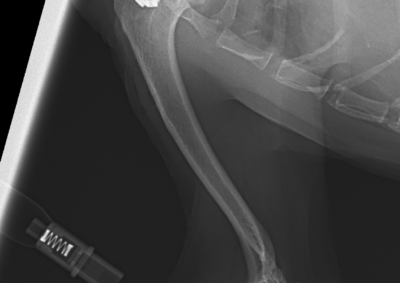

整形外科 注意 ボタンをクリックした先に、治療中および手術中の画像が説明で使用されている場合がございます。 そのような画像に弱い方は閲覧なさらないようお願いいたします。 整形外科 上腕骨外顆骨折の癒合不全 整形外科 大腿骨遠位開放および粉砕骨折 整形外科 膝蓋骨内方脱臼+前十字靭帯断裂 PGR#21+CBLO #251 整形外科 犬の前十字靭帯断裂に対するCBLO #250 整形外科 脛骨粉砕骨折 整形外科 内側鉤状突起分離症(Fragmented Medial Coronoid Process:F... 整形外科 股関節全置換術(トータル・ヒップ・リプレイスメント)#27 整形外科 橈骨固定術 #268 整形外科 橈骨固定術 #267 整形外科 橈骨固定術 #266 整形外科 股関節脱臼に対するBUSTOR #67 整形外科 脛骨粗面剥離骨折 <1234567> 症例カテゴリー 放射線治療整形外科軟部組織外科脳神経外科内科腫瘍外科救急・集中治療リハビリテーション科腫瘍内科内視鏡科脳神経科呼吸器外科中医・漢方猫の腎移植循環器科